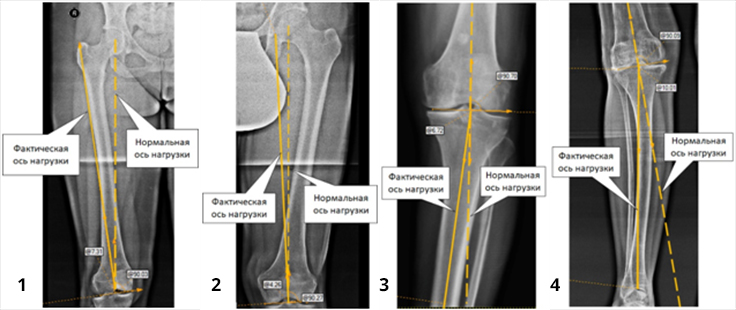

Деформації кісток нижніх кінцівок поділяють на варусні (1 і 3 фото) і вальгусні (2 і 4 фото). Ці деформації часто поєднуються з ротаційними деформаціями, коли вісь сегмента кінцівки додатково повертається або всередину, або назовні. Тоді говорять про складні деформації.

Крім того, що деформації створюють косметичний дефект ( «Х-образні ноги», «ноги кавалериста»), вони призводять до порушення розподілу навантажувальних сил в суглобах, появи болі в суглобах і розвитку артрозу. Своєчасно виявлені й усунені установчі деформації є надійним способом запобігання розвитку артрозу гомілковостопного, колінного і кульшового суглобів.